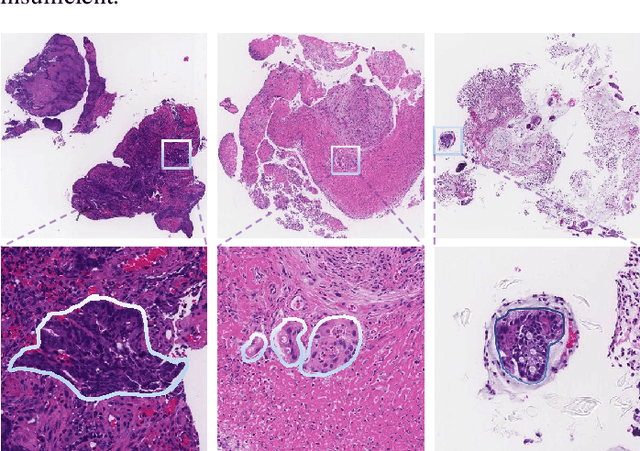

Multi-level colonoscopy malignant tissue detection with adversarial CAC-UNet

The automatic and objective medical diagnostic model can be valuable to achieve early cancer detection, and thus reducing the mortality rate. In this paper, we propose a highly efficient multi-level malignant tissue detection through the designed adversarial CAC-UNet. A patch-level model with a pre-prediction strategy and a malignancy area guided label smoothing is adopted to remove the negative WSIs, with which to lower the risk of false positive detection. For the selected key patches by multi-model ensemble, an adversarial context-aware and appearance consistency UNet (CAC-UNet) is designed to achieve robust segmentation. In CAC-UNet, mirror designed discriminators are able to seamlessly fuse the whole feature maps of the skillfully designed powerful backbone network without any information loss. Besides, a mask prior is further added to guide the accurate segmentation mask prediction through an extra mask-domain discriminator. The proposed scheme achieves the best results in MICCAI DigestPath2019 challenge on colonoscopy tissue segmentation and classification task. The full implementation details and the trained models are available at https://github.com/Raykoooo/CAC-UNet.